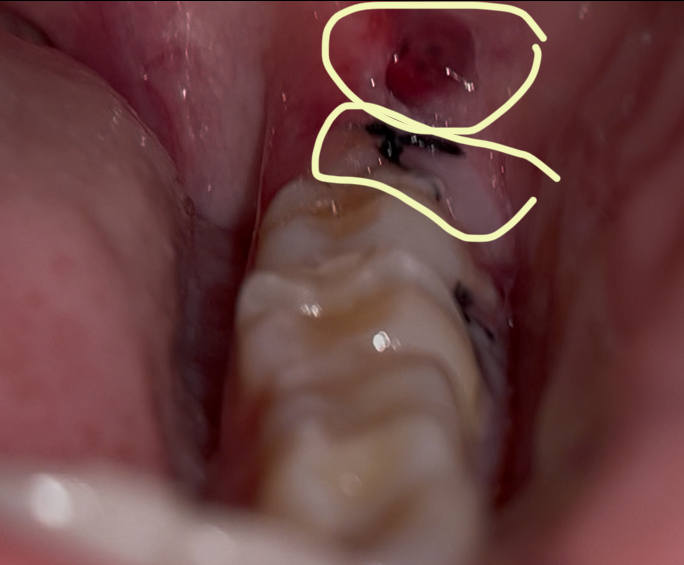

ผ่าฟันคุดครบ1วัน มีสีแดงๆ (วงด้านบน) และ สีขาวเคลือบๆไหม แบบนี้ปกติไหมคะ